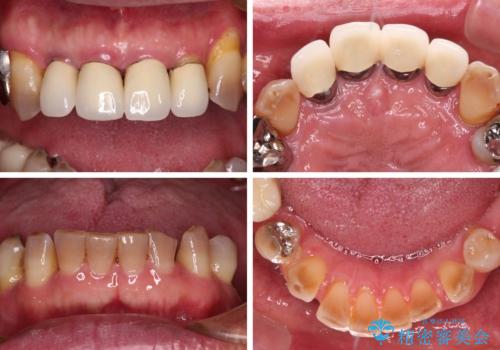

強い咬合力で奥歯がボロボロに インプラント治療による咬合回復と全顎セラミック治療

- 奥歯が咬みにくく、前歯がぐらぐらするとのことで来院された患者様です。

咬合力が強く、奥歯が欠損している状態でした。

欠損部はインプラントによる補綴治療を行うこととし、臼歯部が安定した後に、上下前歯部をオールセラミッククラウンにて補綴治療を行うこととしました。

上顎前歯に歯周ポケットの深い部分がありましたが、インプラントの仮歯で奥歯がしっかりと噛めるようになると、1年程度で深い歯周ポケットは解消されました。

前歯部の審美面も大幅に改善され、大変満足していただけました。